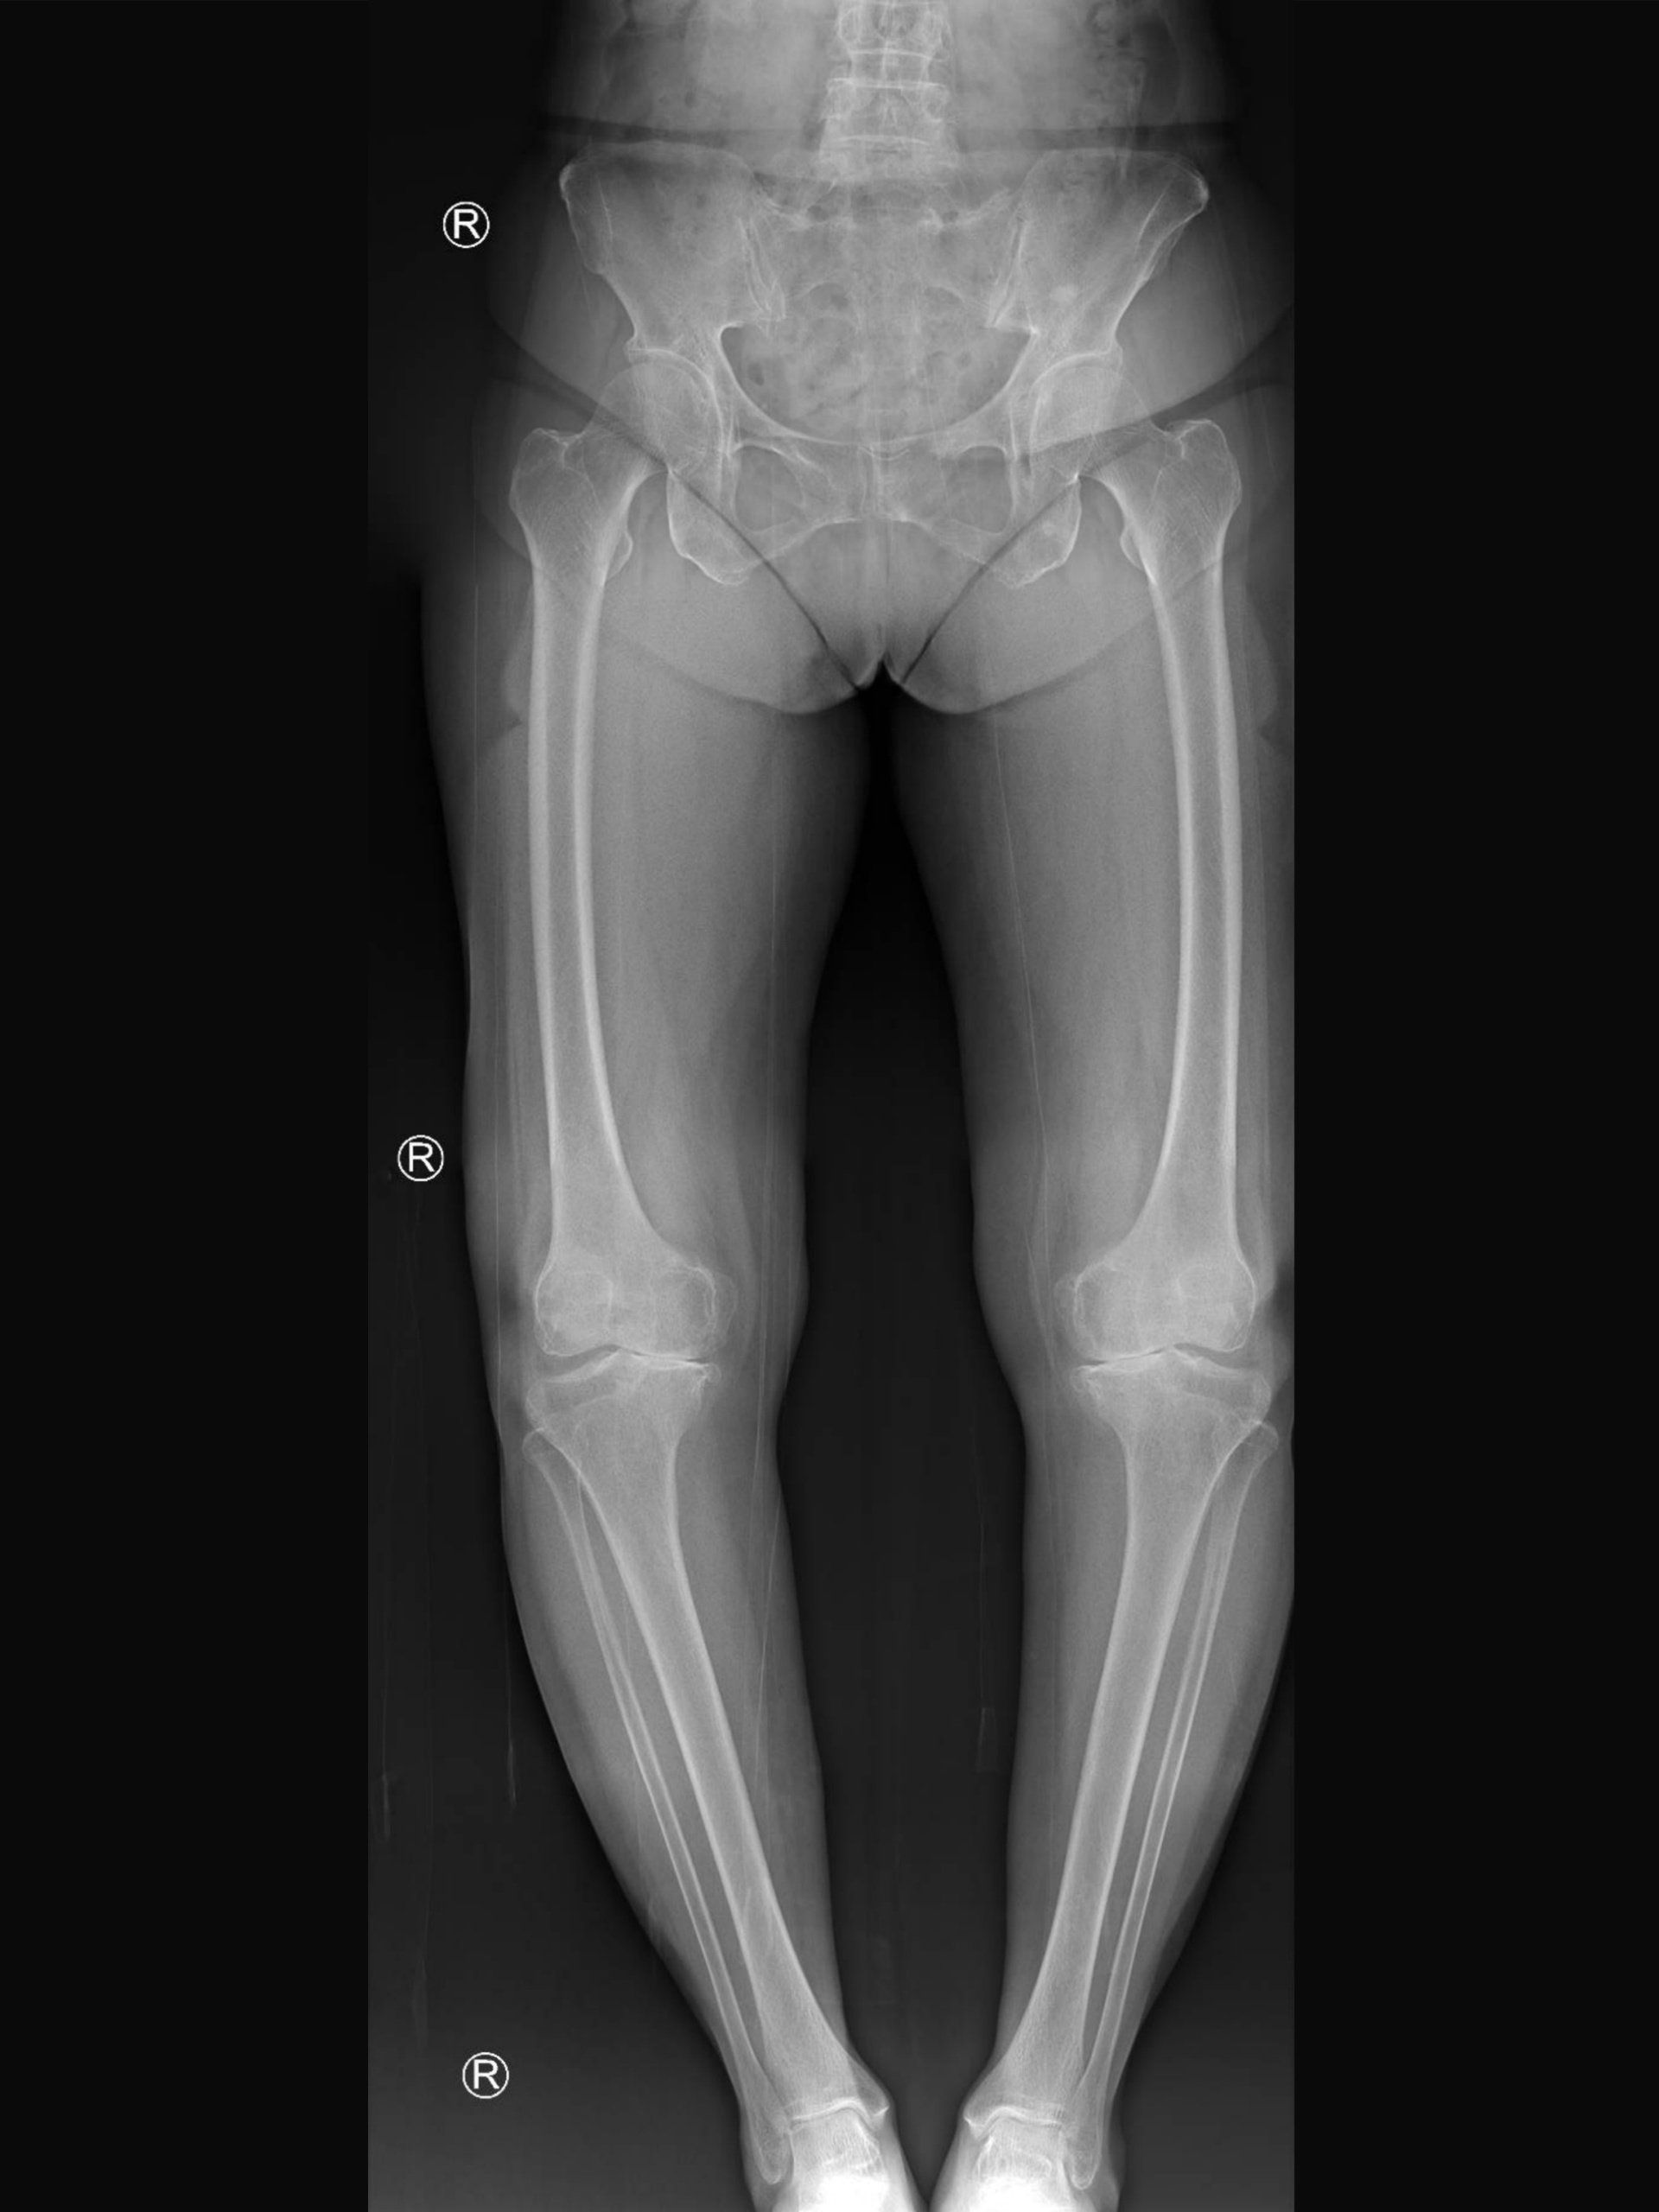

Lower Limb Malalignment

- A line drawn from the centre of the hip to the centre of the ankle should cross the middle of the knee:

- This is called the mechanical axis of the lower limb and shows where the forces act on the knee when standing

- In such a scenario the forces are equally distributed in the knee

What is varus knee deformity?

- When the mechanical axis passes on the medial (inner side) as opposed to the middle of the knee it is because the ankle lies closer to the midline than the knee:

- This is called varus (bow legged) deformity of the knee

What is valgus knee deformity?

- When the mechanical axis falls lateral (outer side) to the middle of the knee it is because the ankle lies further away from the midline than the knee:

- This is called valgus (knock kneed) deformity of the knee